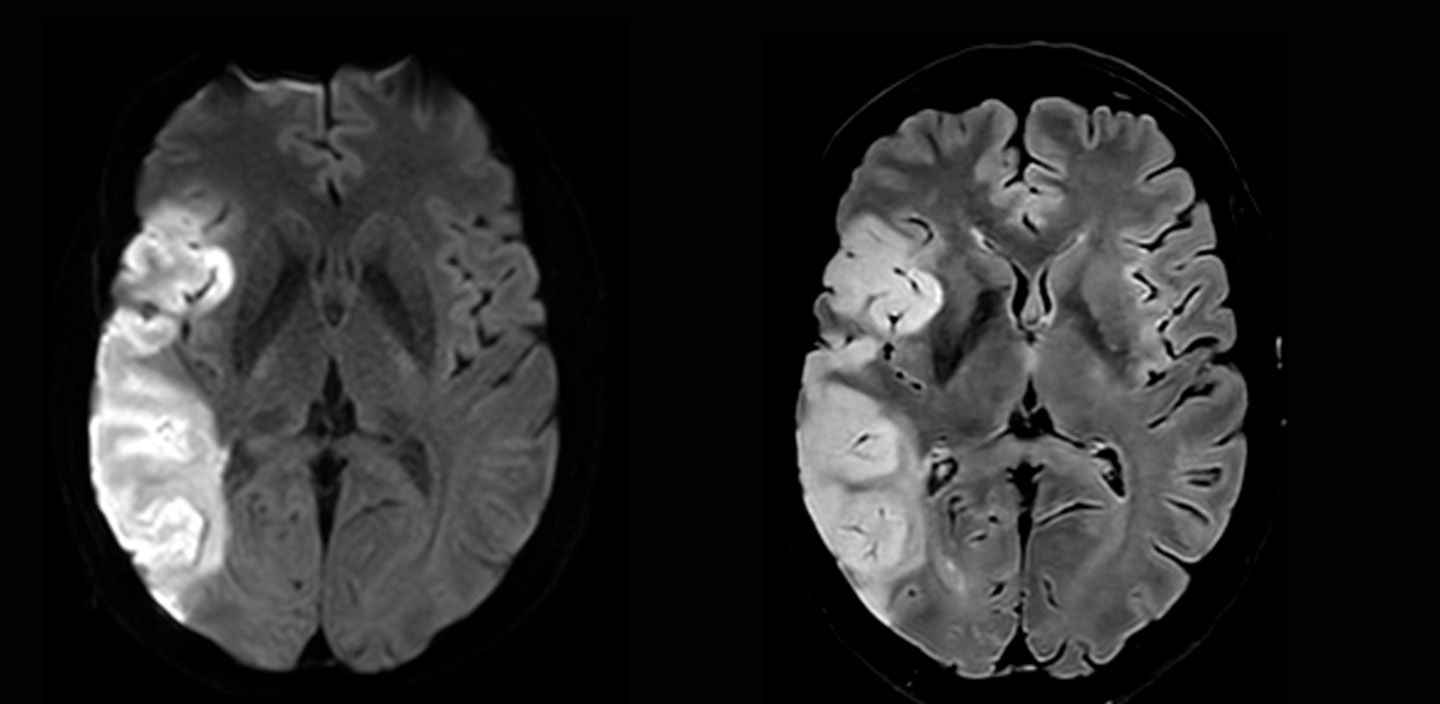

Neuroradiologische Diagnostik eines Schlaganfalls mittels Magnetresonanztomographie (MRT)

MRT (Magnetresonanztomographie)

Ohne Strahlung werden mit Hilfe eines starken Magnetfeldes detaillierte Bilder (sogenannte Sequenzen) von Gehirn, Rückenmark, Nerven, Weichteilen und Knochen erstellt.

CT (Computertomographie)

Es werden Röntgenstrahlen verwendet, um schnelle und präzise Aufnahmen, insbesondere von Weichteilen und Knochen, zu erhalten. Diese Technik ist entscheidend für die sehr rasche und gezielte Abklärung von Schlaganfällen, Hirnverletzungen nach Unfällen bei unklarer Bewusstlosigkeit. Mit Hilfe der Spektraltechnologie können nicht nur die Anatomie und die einzelnen Organe, sondern auch die individuelle Zusammensetzung von Gewebe ermittelt werden, so dass z.B. zwischen Blut, Verkalkung und Kontrastmittel zuverlässig unterschieden werden kann.